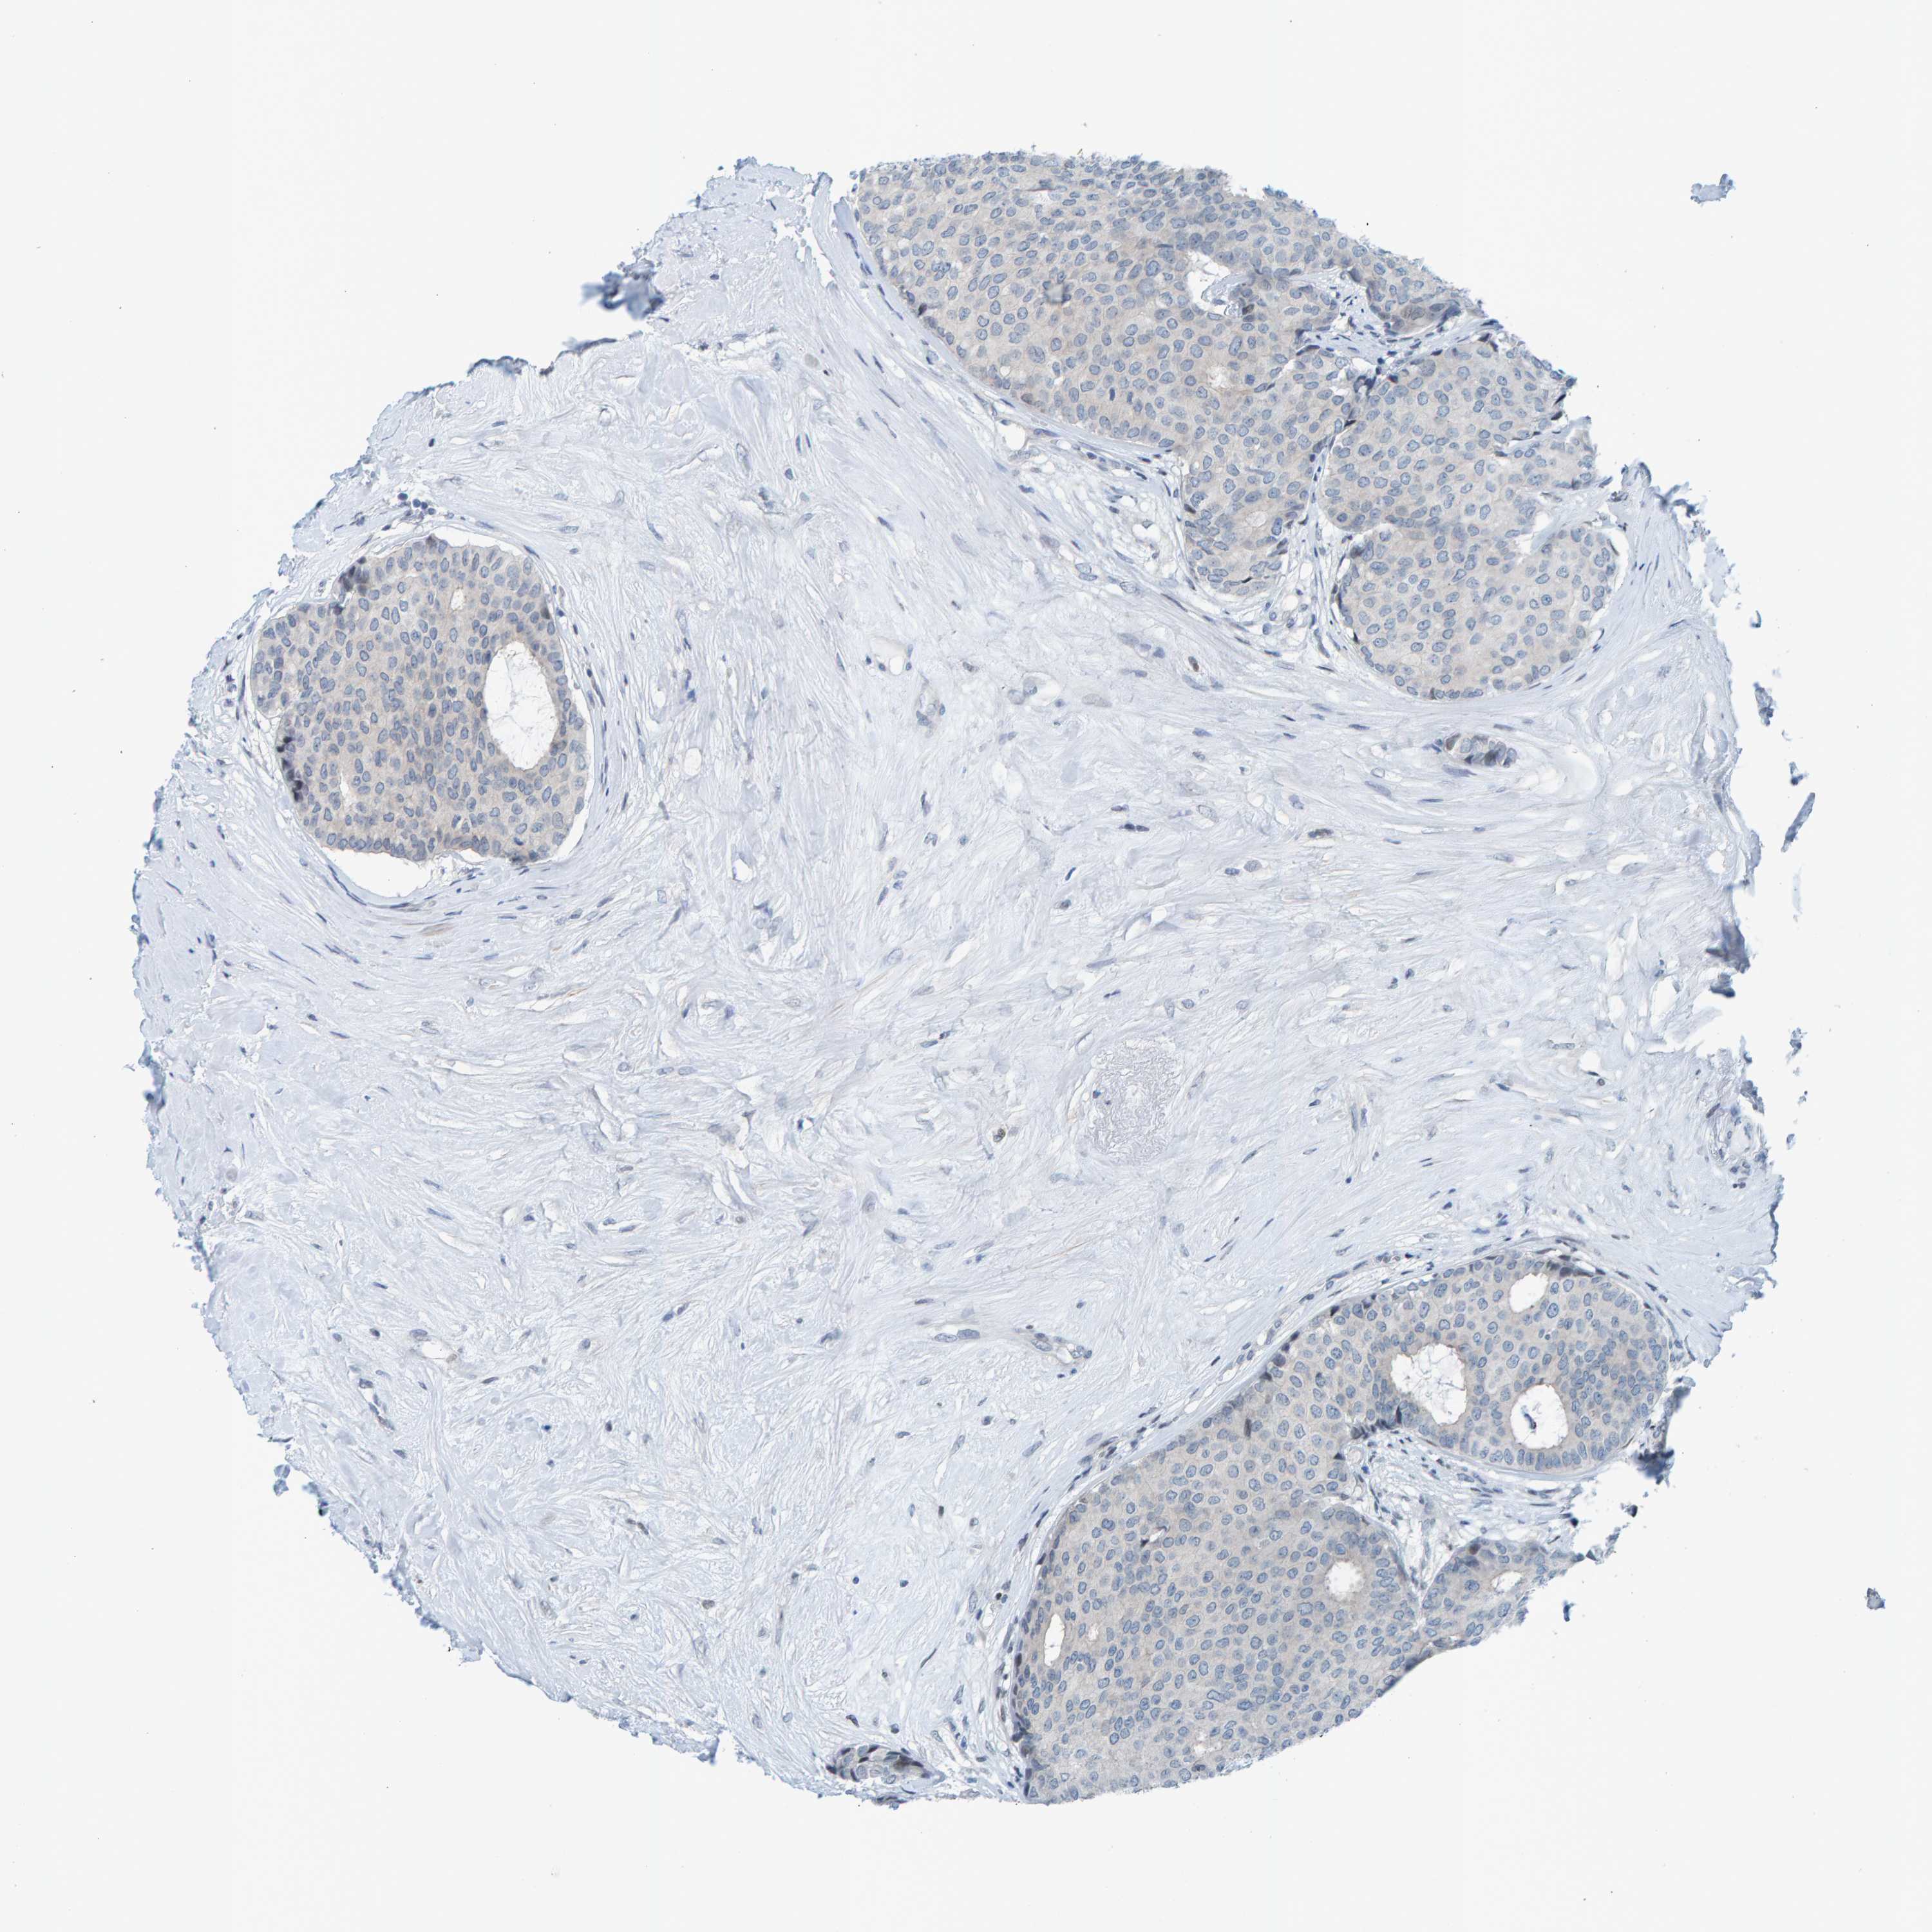

BRCA TCGA BRCA VALIDATION PROTEIN EXPRESSION

ANTIBODIES

AND

VALIDATION